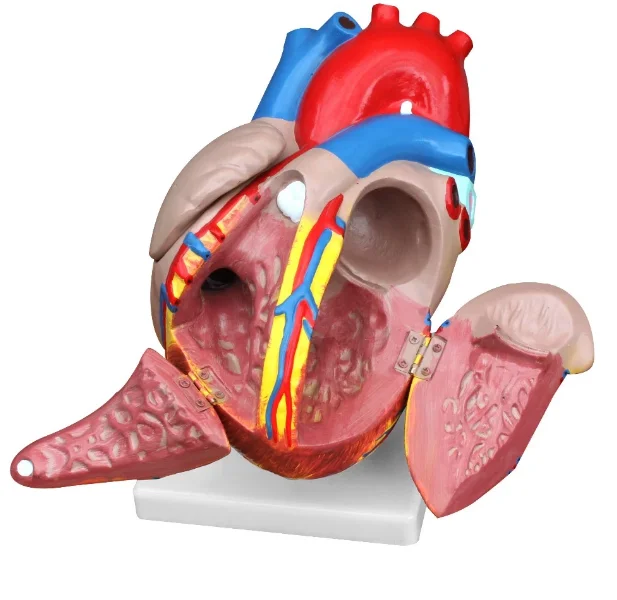

Фотографии и 3D-модели анатомии сердца человека